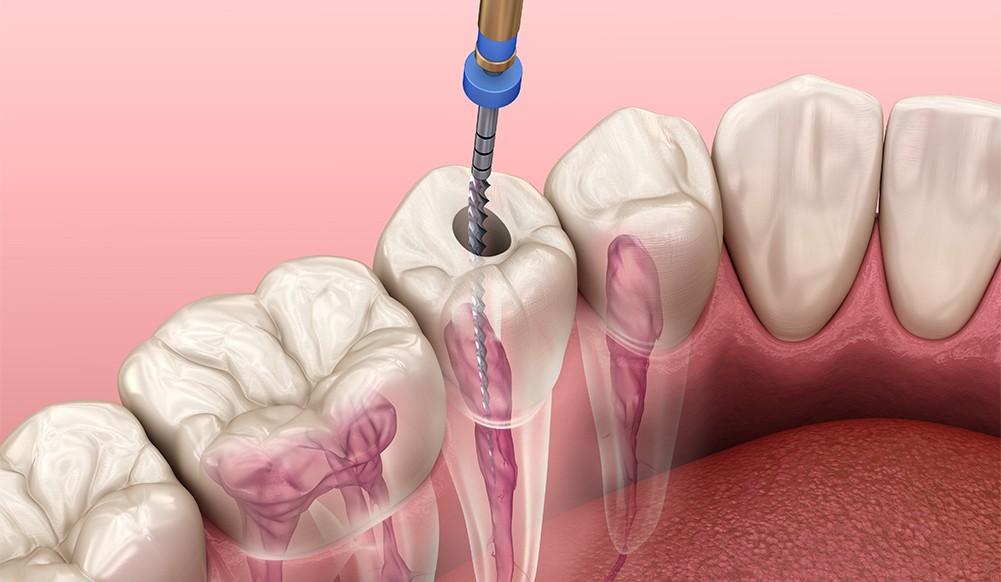

미세현미경 신경치료

치아 속 신경(치수)이 충치·균 감염·외상으로 손상되면 극심한 통증이 시작됩니다. 신경치료(근관치료)는 이 감염된 신경과 혈관을 제거‧소독해 발치 대신 치아를 보존하는 마지막 방법입니다.

왜 ‘미세 현미경’이 중요한가요?

육안의 한계를 넘는 최대 25배 확대 시야로, 뿌리 끝까지 환히 들여다보며 치료합니다.

정밀 진단 – 눈에 보이지 않던 잔존 감염·미세 균열까지 포착

오차 없는 치료 – 머리카락 굵기보다 가는 세근관도 깔끔히 청소·형성

재발 차단 – 감염 부위를 완전히 제거하고 밀폐해 실패율을 대폭 감소

미세 현미경 신경치료의 핵심 장점

높은 성공률 : ㎛ 단위 정밀 시술로 재치료 확률 최소화

치료 시간 단축 : 정확도가 높아 불필요한 내원·재시술을 줄임

통증·부작용 감소 : 손상 조직만 선택적으로 제거해 회복이 빠름

자연치아 보존 극대화 : 뿌리 구조를 최대한 보존해 수명 연장

자연치아는 인공치아보다 더 소중합니다.

미세 현미경 신경치료로 통증을 잡고, 치아를 끝까지 지켜 드립니다.